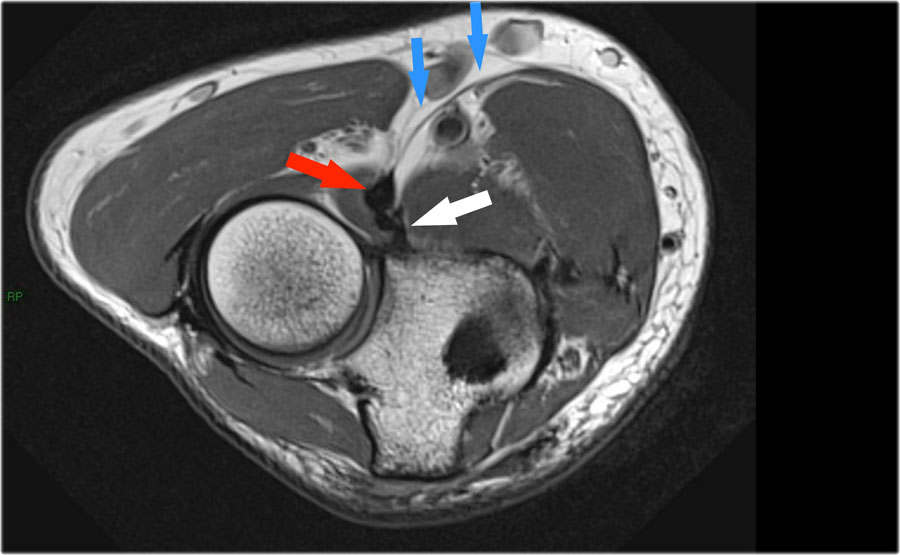

- Nếu bạn nhìn vào mỏm trên lồi cầu trong, bạn sẽ nhận thấy bó sau như một cấu trúc mỏng (mũi tên xanh).

- Notice the ulnar nerve sitting in the cubital tunnel.

- The posterior bundle forms the floor of the cubital tunnel.

- A retinaculum covers the cubital tunnel.

- Lưu ý rằng bó trước dày hơn nhiều (mũi tên trắng).

- Bạn có thể thấy sự khác biệt giữa dây chằng trước và dây chằng sau mặc dù chúng tạo thành một dây chằng duy nhất.

- Khi đi về phía xa, chúng ta sẽ thấy chúng hợp nhất lại để bám vào củ sublime.